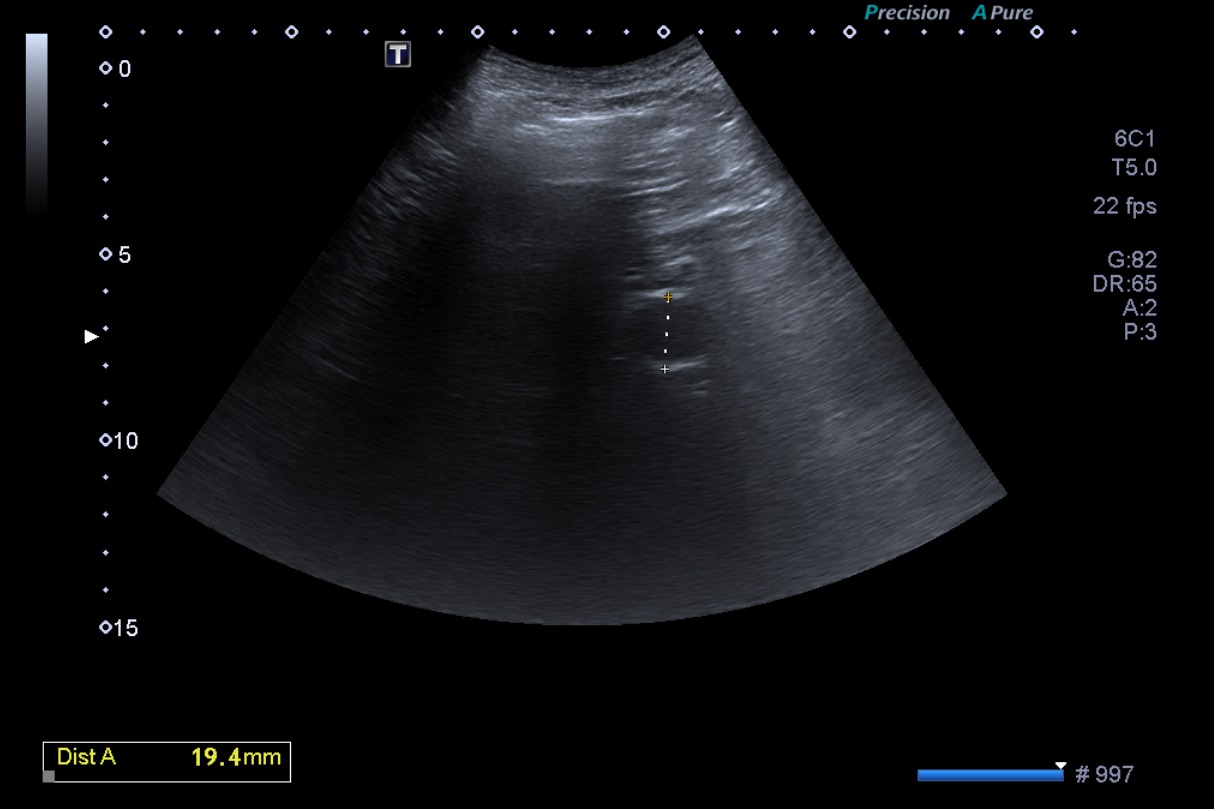

• Anamnesis y exploración: el paciente consultó hace un año por dolor en miembros inferiores, que se iniciaba con la deambulación y cedía con el reposo. Con exploración osteomuscular normal y sin palparse pulsos pedios, se solicitó ecografía para descartar aneurisma de aorta e iliacas. (Ecografía 1).

• Ecografía 1 (hace 1 año): segmento de aorta visible de 2 cm de diámetro, arterias ilíacas no accesibles. Leve ectasia de venas suprahepáticas y vena esplénica. Ligera dilatación de la vía biliar intrahepática. Hígado de morfología y ecogenicidad conservada, nódulo ecogénico bien delimitado en lóbulo derecho de 2,5 cm, compatible con hemangioma.